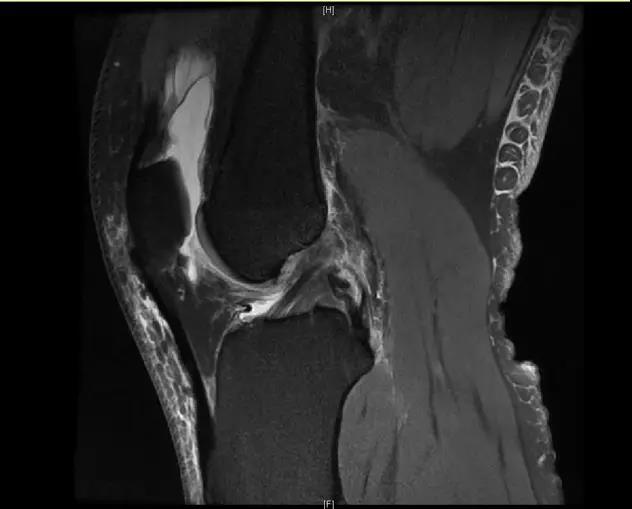

【有声病例】后交叉韧带断裂

【朗润影像档案】20180330磁共振影像病例结果讨论

【朗润影像档案】磁共振影像病例分享(编号20180330)